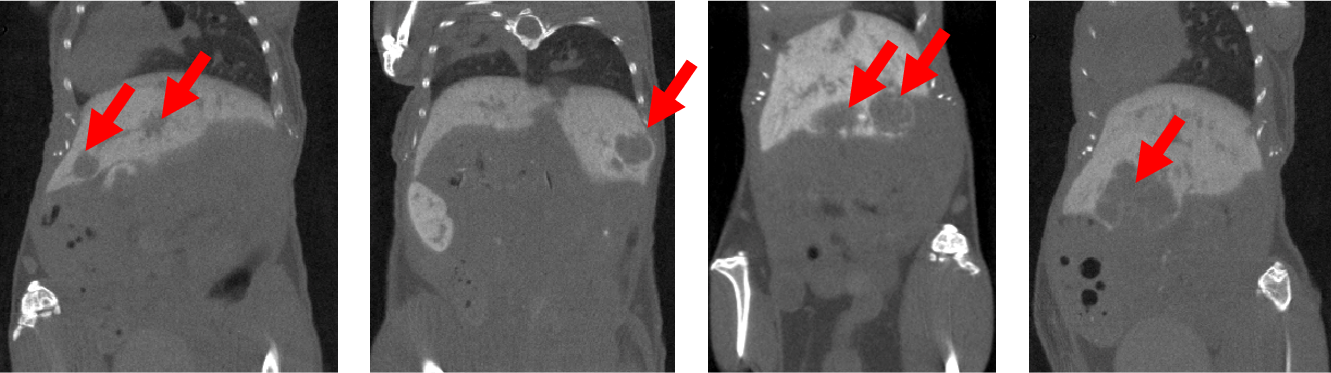

6、對比增強腫瘤CT成像

腫瘤研究:對比增強CT檢查活體小鼠肝腫瘤:注射顯影增強劑Exitron 12000,F(xiàn)DK重建,成像時間:4min,100μm voxel size。

腫瘤成像.png